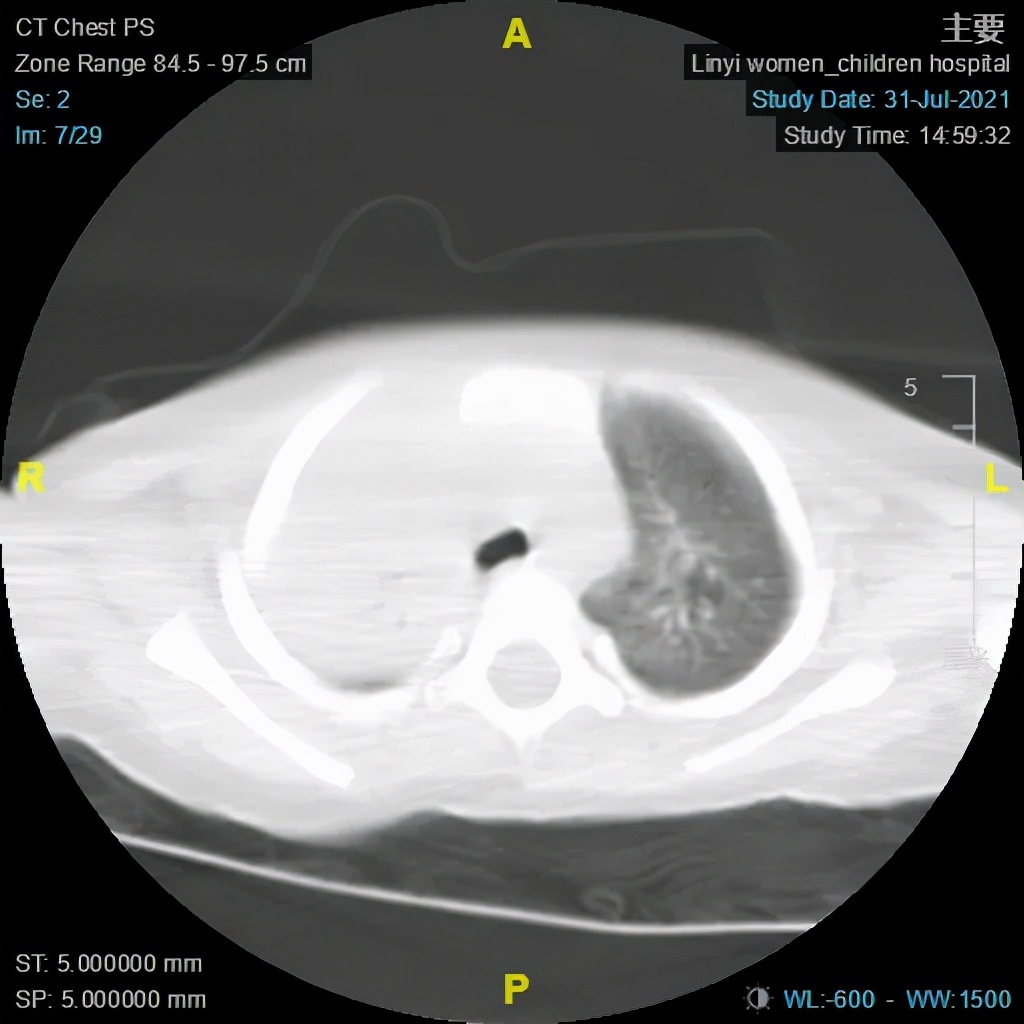

大叶性肺炎术前及术后CT对比图

(电子支气管镜、支气管肺泡灌洗术术后)